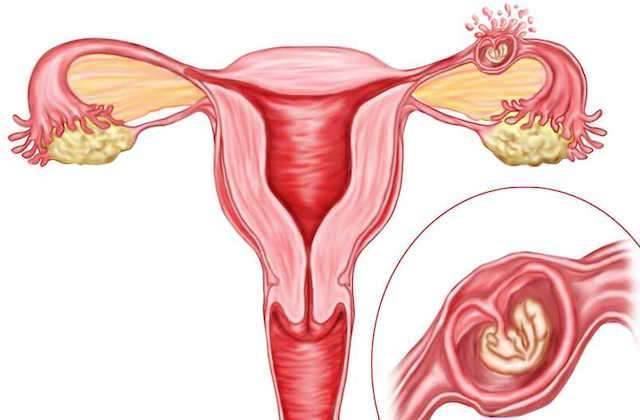

من الإخصاب إلى الولادة، يتطلب الحمل عددًا من الخطوات في جسم المرأة. إحدى هذه الخطوات هي عندما تسافر البيضة المخصبة إلى الرحم لتثبيتها. في حالة الحمل خارج الرحم، لا ترتبط البويضة المخصبة بالرحم. بدلاً من ذلك، قد يعلق على قناة فالوب أو تجويف البطن أو عنق الرحم.

على الرغم من أن اختبار الحمل قد يكشف أن المرأة حامل، فإن البويضة المخصبة لا يمكن أن تنمو بشكل صحيح في أي مكان آخر غير الرحم.